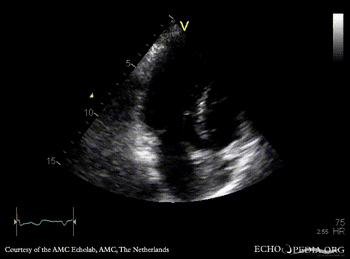

E00504.gif E00505.gif

A4CH: concentric hypertrophy of left ventricle, SAM of AMVL A3CH